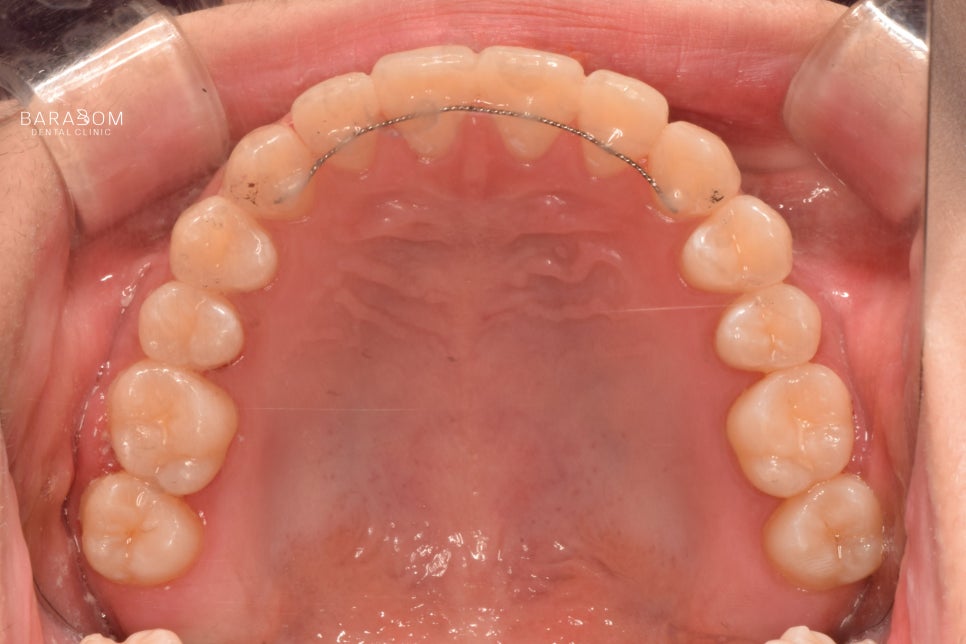

| 종결

치료를 받은 지 17개월 가량이 지난 후 모습입니다.

1️⃣반대 및 절단 교합 양상이

모두 해소되었으며,

2️⃣골격적인 문제의 한계를 넘어

아랫턱과 윗턱이 조화를

이루는 모습이 관찰됩니다.

또한 윗니가 아랫니를 덮으며

정상적인 피개량을 가지고 있는데요,

하악 전체 치열 후방 이동과

상악 앞니의 정출을 통해

교합의 안정과 함께

심미를 되찾은 모습입니다.